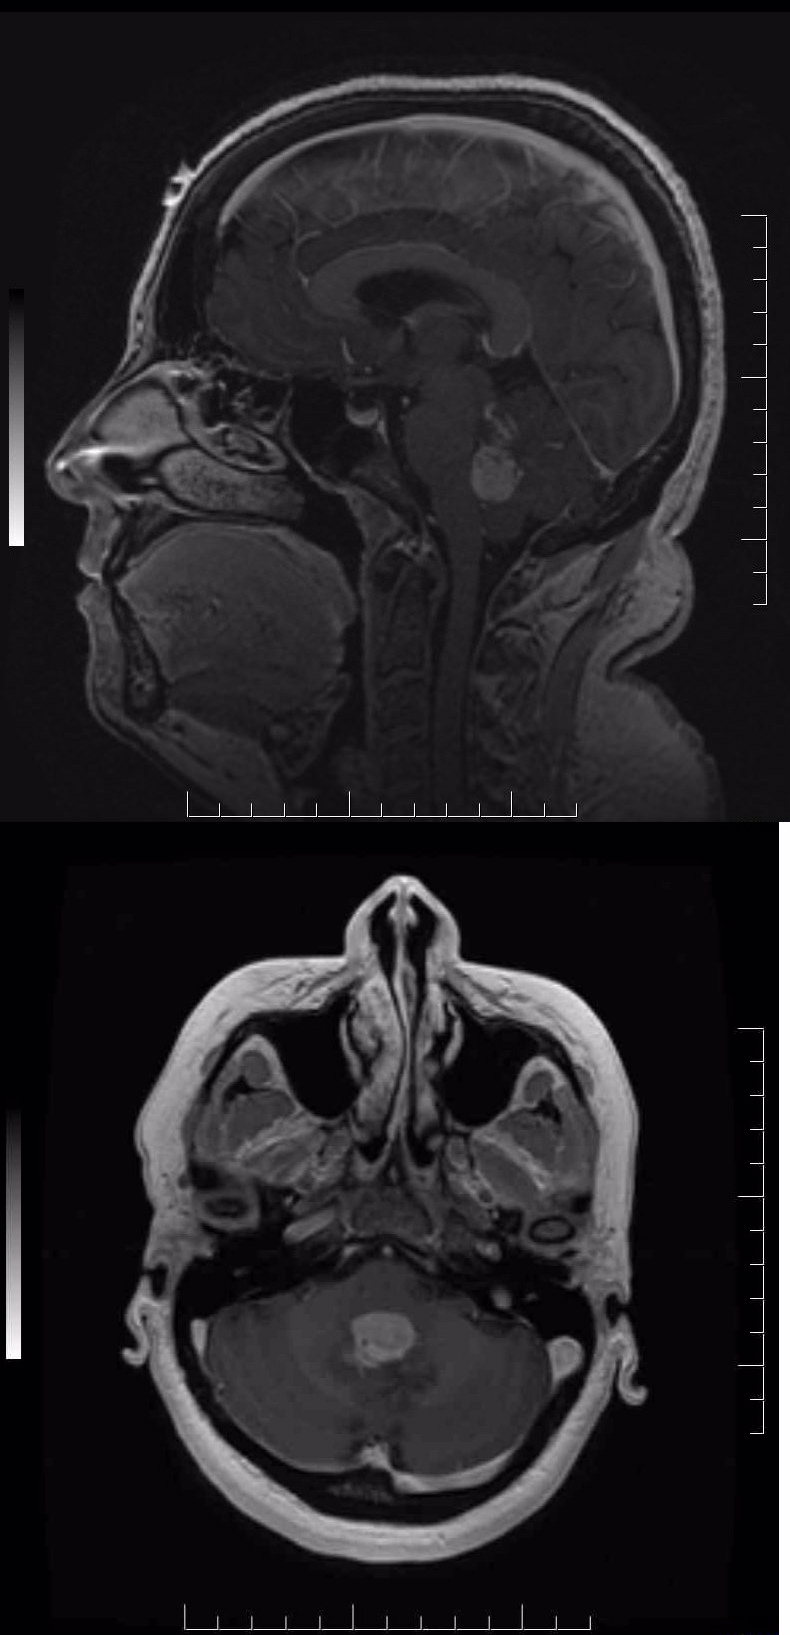

MRI_sagittal__&_axial_view…